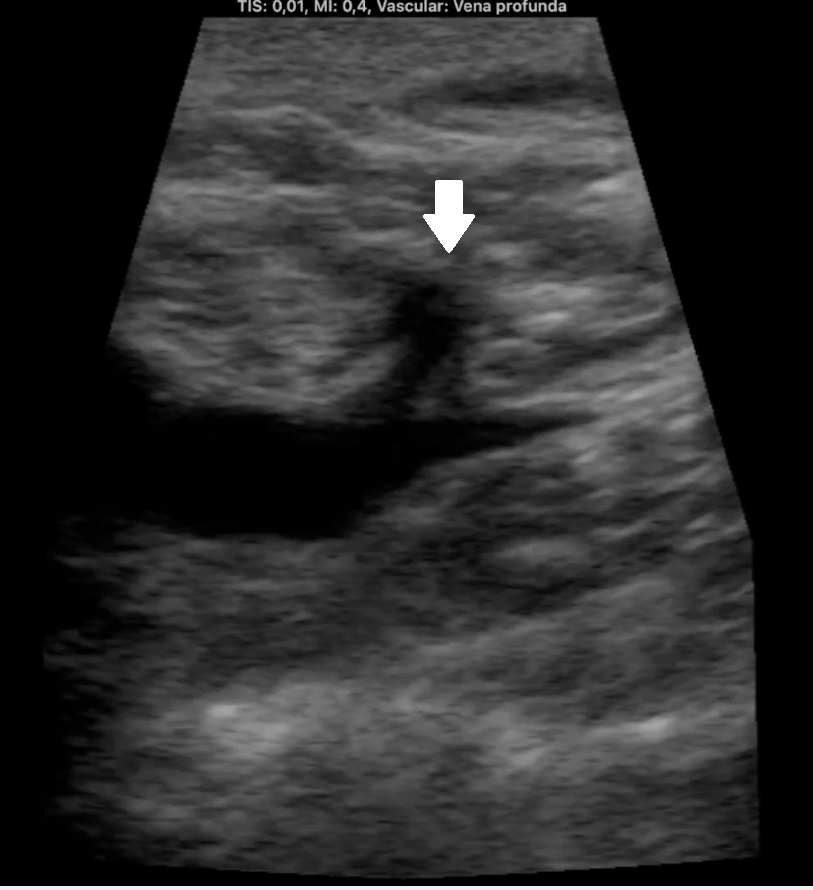

Descripción de los hallazgos ecográficos y las imágenes más relevantes para la resolución del caso

Ocupación de espacio con trombo venoso ecogénico desde poplítea hasta tercio superior, así como safenas externa e interna (imagen 2 femoral profunda e imagen 3 safena mayor). Lesión isoecogénica en segmentos hepáticos V/VI de 6,65 x 5,87 cm (imagen 4).

En urgencias hospitalarias LDH 383, FA 133, GGT 88, BT 1,21, DD 19898. Ecografía de MID realizada por cirugía vascular.

Masa hepática sospechosa de malignidad. TVP MID secundario a lo previo que se confirma por cirugía vascular. Diagnóstico diferencial con metástasis hepáticas y estirpe hepatobiliar.